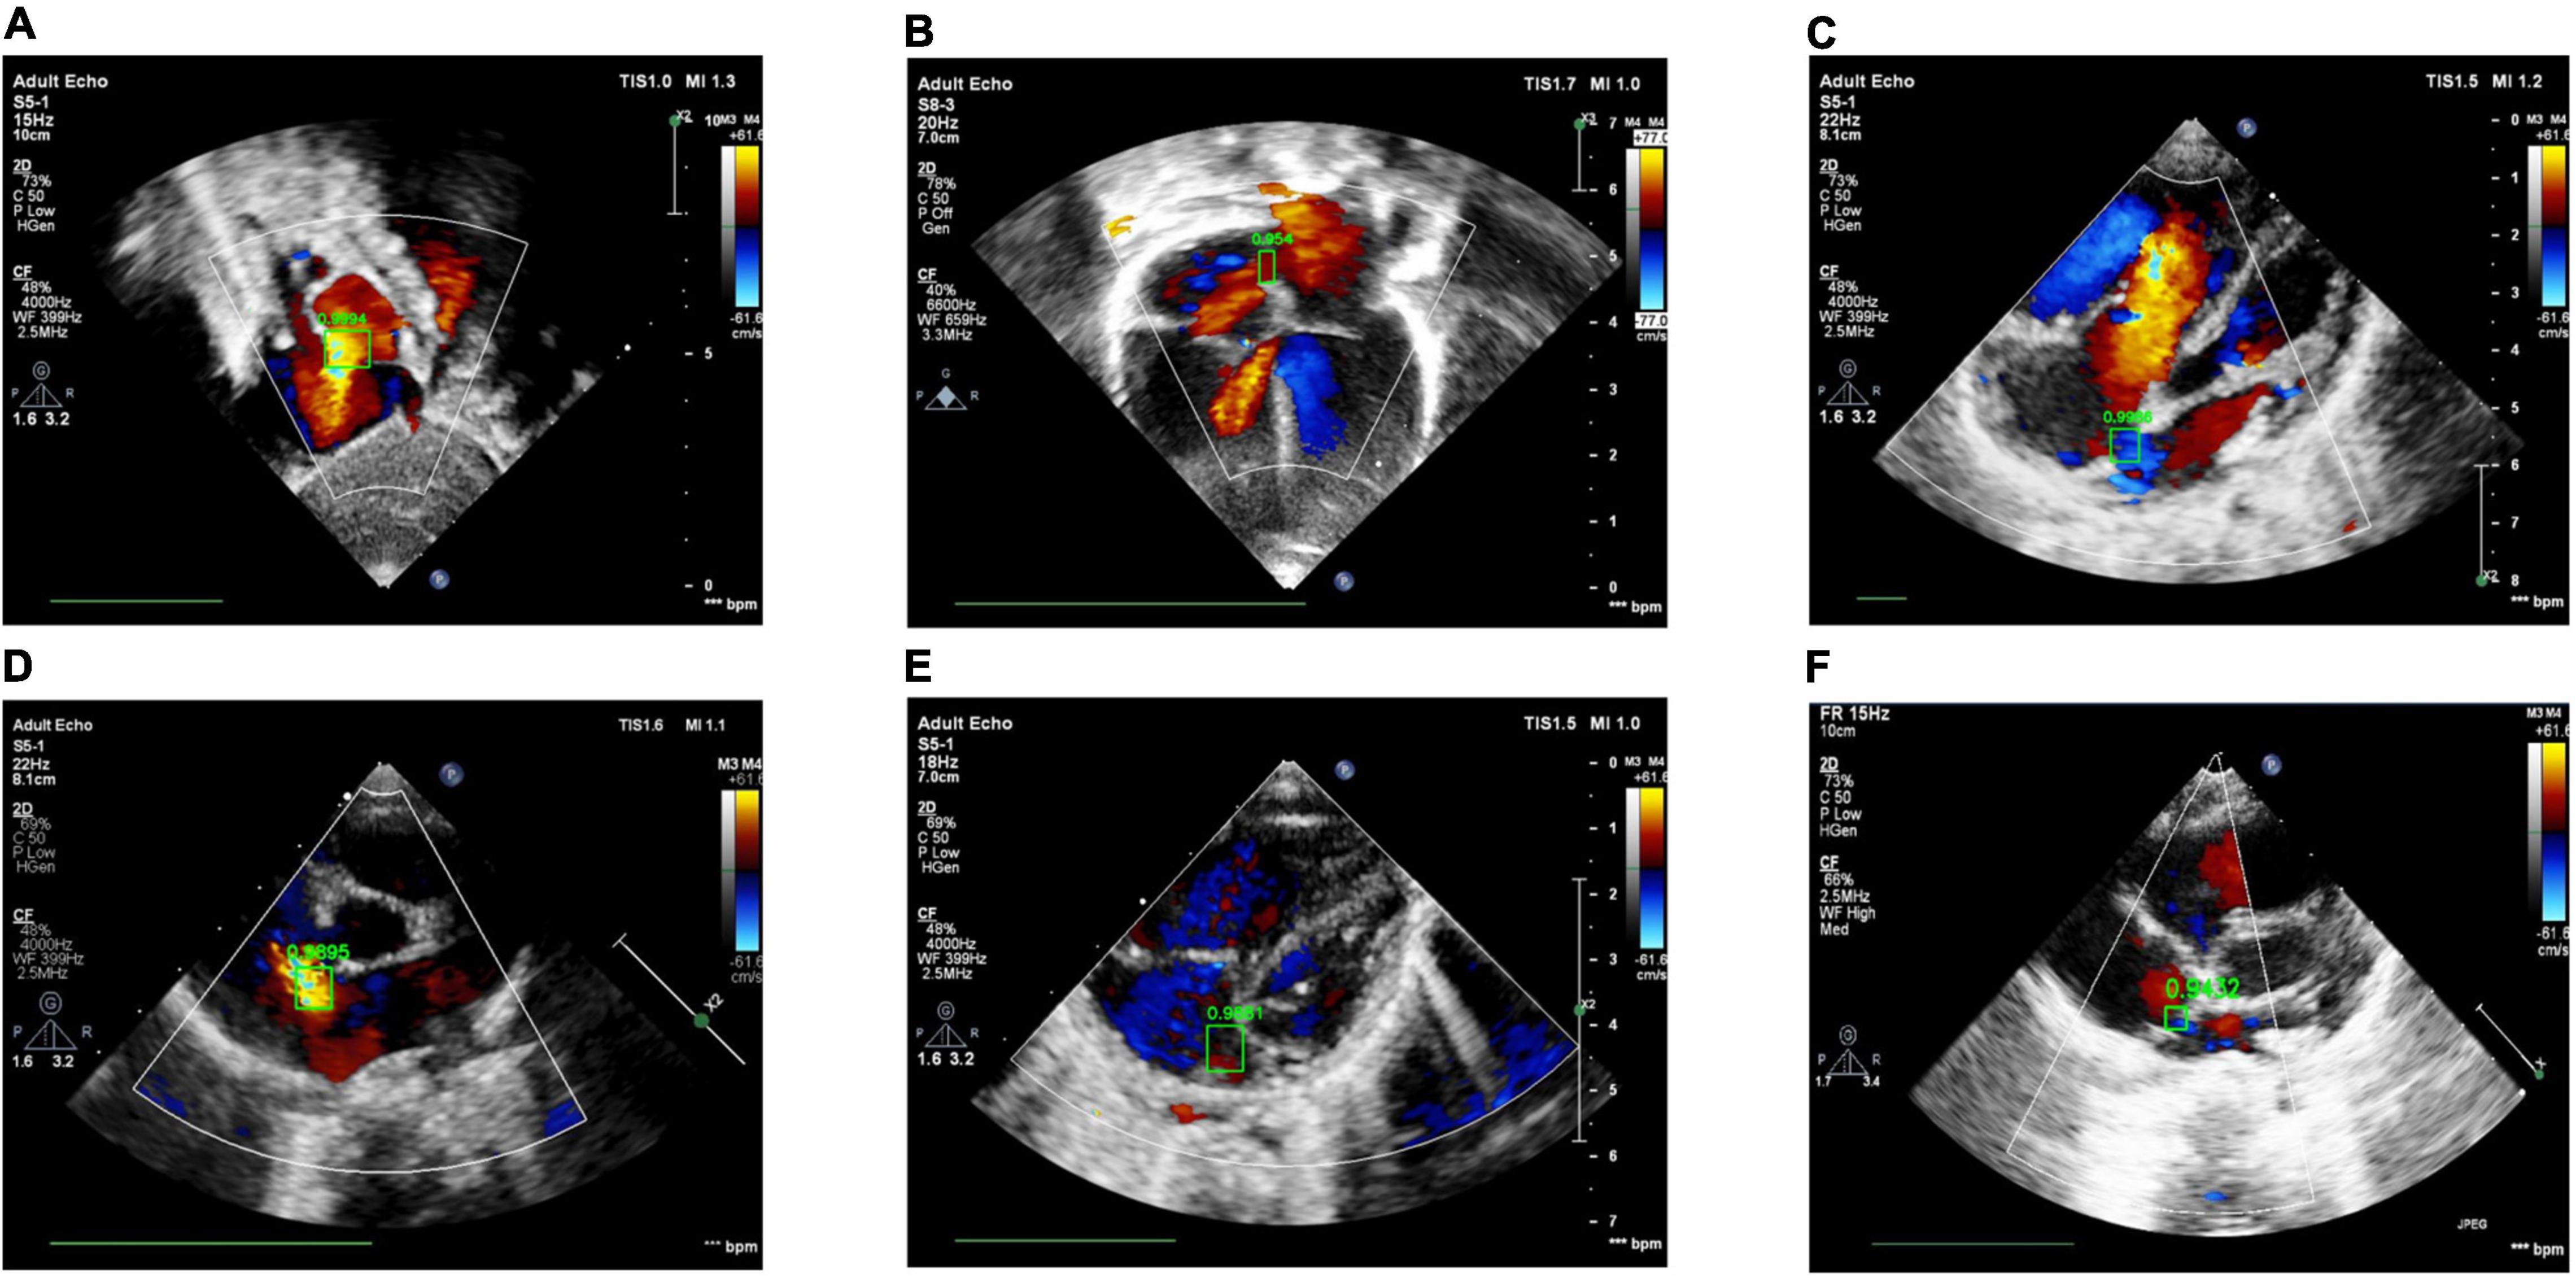

The ROC Curve of the ASD detection model on the four target echocardiographic views was illustrated in Figure 8. The AUC of subAS was the highest, reaching 0.8965, and the AUCs of the other three views were roughly at the same level, indicating that the model had a stronger ASD detection ability in the view of subAS. In this study, the optimal cut-point was determined by calculating the maximum value of Youden Index. According to the analysis of AUC curves, the optimal cut-point was 0.95. Therefore, cases that are not detected or have a confidence level lower than 0.95 were considered as negatives and cases with a confidence level greater than or equal to 0.95 were regarded as positives. Figure 9 also showed example successful and failure cases of ASD detection. The ASD detection performances of before and after the detection refinement were compared in Table 6. The average values of Accuracy, Recall, Precision, Specificity, and F1 Score for image-level ASD detection before the detection refinement were 0.8699, 0.8608, 0.8208, 0.8744, and 0.8397, respectively, while the average values of Accuracy, Recall, Precision, Specificity, and F1 Score for image-level ASD detection after the detection refinement were 0.8833, 0.8545, 0.8577, 0.9136, and 0.8546, respectively. It can be seen that Accuracy, Precision, Specificity, and F1 Score have increased by 1.34, 3.69, 3.92, and 1.49%, respectively, while the recall rate has been reduced by only 0.63%. The p-values of the t-test indicated statistically significant differences in ASD detection before and after the refinement module for all performance metrics in all other views except the LPS4C view. As for view LPS4C, the differences in ASD detection before and after the refinement module were statistically significant in terms of recall, precision, and specificity, but not in terms of accuracy and F1 score. In addition, a preliminary case-level study has also been conducted where a threshold of 0.6 was used based on a prior from experienced physicians. As shown in Table 6, the average values of Accuracy, Recall, Precision, Specificity, and F1 Score for case-level ASD detection before the detection refinement were 0.9888, 0.8381, 0.8786, 0.9214, and 0.9072, respectively, while the average values of Accuracy, Recall, Precision, Specificity, and F1 Score for case-level ASD detection after the detection refinement were 0.9897, 0.9143, 0.9318, 0.9563, and 0.9505, respectively. A thorough grid-search based approach can be performed to find the optimal threshold in future studies when larger test sets are available.

Figure 9. Examples of success and failure cases. (A) ASD detected in the subAS view: bright red shows the transeptal flow with left-to-right shunt, (B) ASD detected in the A4C view: dark red in the center of the atrial septum indicates the occurrence of left-to-right shunt flow, (C) ASD detected in the LPS4C view: blue regions represent the transeptal flow with right-to-left shunt, (D) ASD detected in the PSAX view: bright red shows the transeptal flow with left-to-right shunt. (E) ASD detection of false positive, due to the confusion of similar structures and the failure of the cardiac anatomy segmentation stage; (F) ASD detection of true negative, due to the low confidence (0.9432 < 0.95).